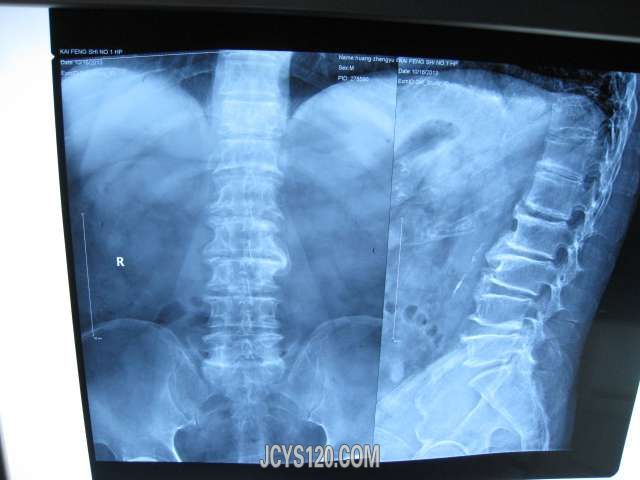

• 针对这种腰疼用什么方法治疗好 attach_img

• huangdz 2014-10-3

• 患者男性,85岁,自诉腰疼3年 患者除腰疼外,无其他不适,平时比较注意身体锻炼(慢跑i),身体比较健康,血压、血糖均正常。无不良嗜好。几年来腰疼严重时,自行口服消炎止痛药(双氯芬酸片、氯唑沙宗片、 ...  阅读全文>